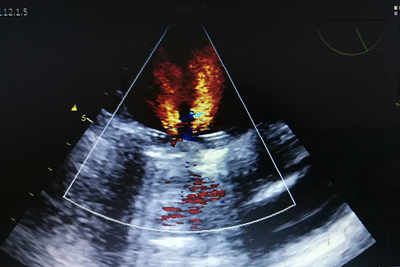

已开展经食管超声心动图(transesophageal echocardiography,tee)检查

快讯】市二医院开展一项更清晰的"彩超"技术— 经食道超声心动图检查